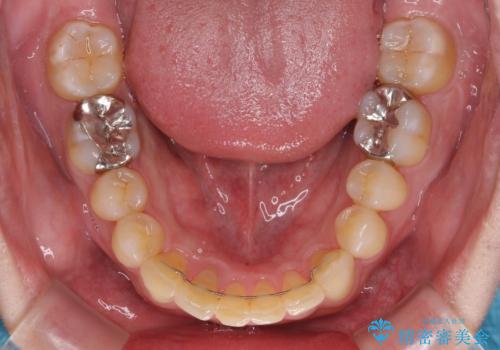

- 深い咬み合わせによる食いしばりで、顎関節や頭が痛むことがあるとのことで来院された患者様です。

歯ぎしりができないくらい強い食いしばりの咬合状態であったため、奥歯の歯軸を起き上がらせることで咬合を挙上させ、歯ぎしりができるようにしていくこととしました。

下顎が左側にずれているため、上下正中は最大限合わせられるところまで合わせるゴールとなりました。